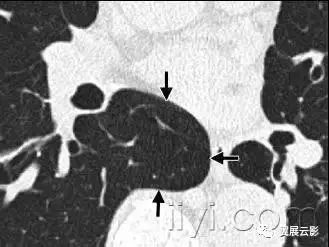

四十、曲菌球

病理:曲菌球是孤立的菌丝相互缠绕形成的肿块,常是曲菌类病原,黏液、纤维素、细胞碎片共同构成空洞成分,常发射跟你在纤维空洞的基础上(例如结核或者结缔组织病)

平片和CT:曲菌球可以随着体位的变化发生变化,部分病例可见空气新月征(图)CT上可以呈现海绵样影像和曲菌球内的钙化灶。同义词是真菌球。